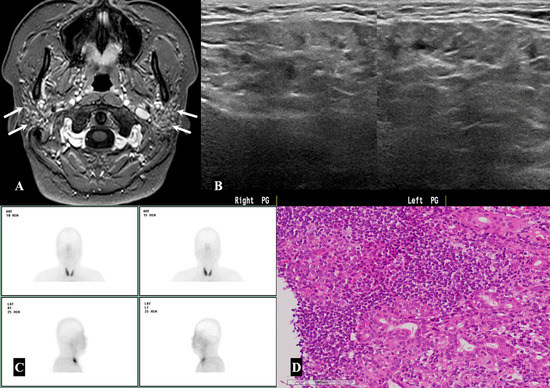

2. Materials and Methods

2.3. Assessment of Incidental Parotid Lesions: Image Analyses